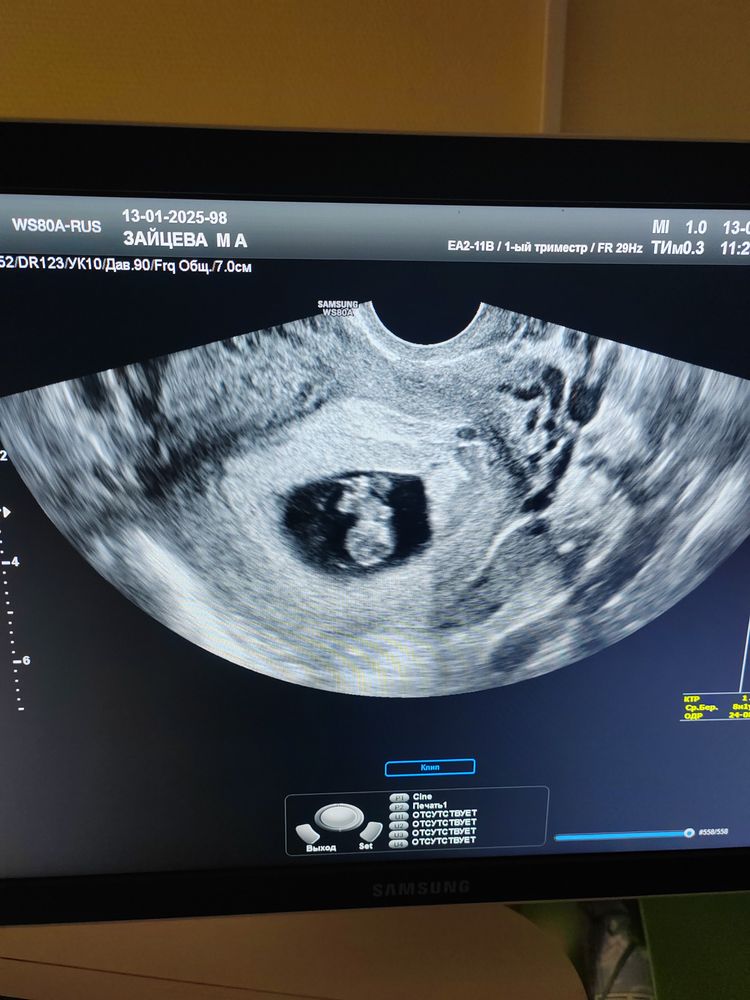

Мария Зайцева в Благополучная беременность год

вот такие мы большие уже, срок по мес 7 недель и 5 дней, по узи 8,1. Ктр 17 мм